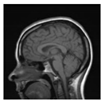

| Original Image | Marked Image | Encrypted Image (DRPE) | Decrypted Image | Correlation between Extracted Blocks and Original Blocks |

![]() | ![]() PSNR = 34.26 dB SSIM = 0.96 | ![]() PSNR = 12.84 dB SSIM = 0.0349 | ![]() PSNR = 34.37 dB SSIM = 0.96 | ![]() |